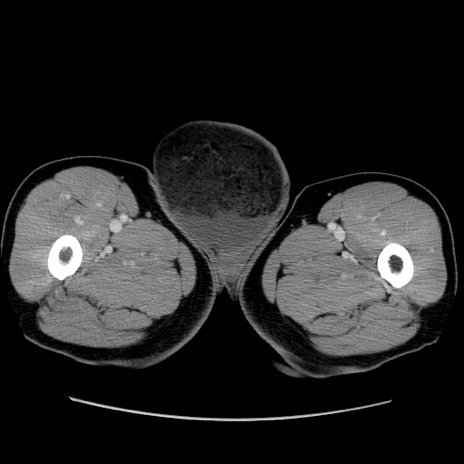

症例34(横断像)

【症例】60歳代 男性

【主訴】右鼠径部膨隆

【現病歴】1年程前より右鼠径部膨隆あり。自己にて還納可能だったため放置していた。3時間前より右鼠径部の脱出を認め、還納困難となり受診。

【既往歴】高血圧

【身体所見】右鼠径部に小児頭大の膨隆あり。弾性硬であり、用手還納は困難。左鼠径部にも膨隆を認める。脱出はなし。

【データ】WBC 15500、CRP 測定なし